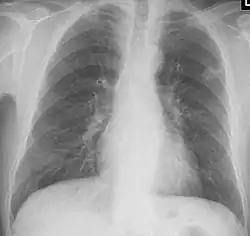

Speziell im Fall eines 3D-Datensatzes werden häufig Schnittbilder oder Schnittbildserien des Körpers errechnet. Die Orientierung der Schnittbildebene und die Position sind dabei meist frei wählbar. Im Gegensatz zu einem Projektionsverfahren wie der Durchstrahlung eines Körpers können so gezielt Details oberhalb oder unterhalb der interessierenden Schicht ausgeblendet werden. Im unteren Beispiel wurde durch die Technik der Schnittebene die störende Information der Rippen entfernt. Teilweise werden für die Diagnose oder Auswertung auch 3D-Rekonstruktionen erstellt, die sich beliebig im Raum orientieren lassen und Anblicke von allen Seiten erlauben.

Projektion (normale Röntgenaufnahme) -

Schnittbild in Körperlängsachse (frontaler Schnitt)

-

transversales Schnittbild des Körpers